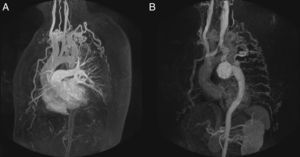

Patient 1, a 57-year-old man in NYHA class III with severe aortic regurgitation and dyspnea, required percutaneous coronary intervention before surgery. Numerous collateral vessels had complete obstruction of the aorta and a giant intercostal aneurysm below the coarctation point (Fig. 1). The aortic obstruction was treated using the technique described and a CS was implanted to exclude the aneurysm. The final outcome was very good; the gradient disappeared and there was a large increase in lumen diameter. We also performed redilation and obtained good apposition of the distal stent edge. The aneurysm could be visualized very faintly following the final injection (Fig. 2). Two days later, the end was tragic when the patient suffered a massive hematemesis and died. Autopsy showed that although the coarctation was well repaired and the stent did not have its cover, leaving the aneurysm in communication with the descending aorta. We believe that the large increase in systolic blood pressure from 70mmHg to 150mmHg after the coarctation point led to a high-pressure retrograde flow into the aneurysm. In the following hours, the aneurysmal bulge ruptured into the esophagus, with fatal gastrointestinal bleeding (Fig. 3).

Figure 2.Coarctation with complete aortic obstruction and giant intercostal aneurysm (patient 1). A, aortography of the arch showing the complete obstruction with the snare in position; B, in the late phases, in 40° left anterior oblique view, large collateral vessel (arrows) that provides circulation into the descending aorta contrasted with a large intercostal aneurysm (arrowheads); C, perforation with Crossit 300 guide wire and insertion into the GooseNeck™ snare; D, guide wire captured with the snare and extraction establishing the radial-femoral line; E, expansion with 2mm×20mm Maverick coronary balloon catheter; F, inversion of the loop, positioning of the 0.035 guide wire, and expansion of the 8mm×20mm Balt balloon catheter; G, positioning the covered stent; H, expansion; I, outcome with good stent apposition to the wall.